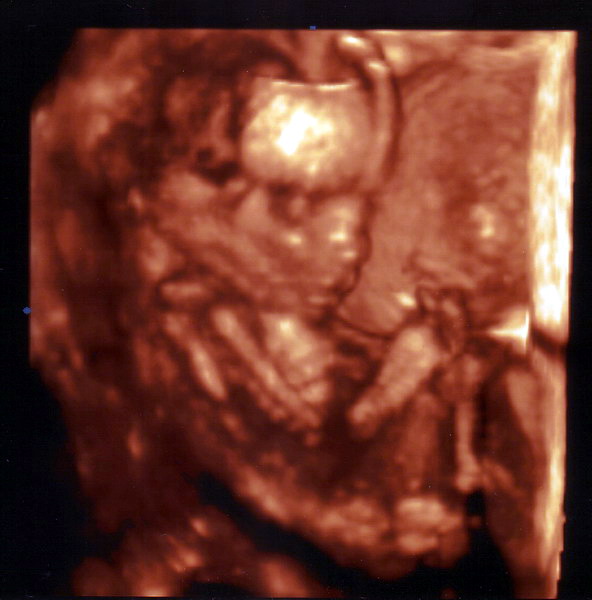

Keny nagyon cuki Kornélka!